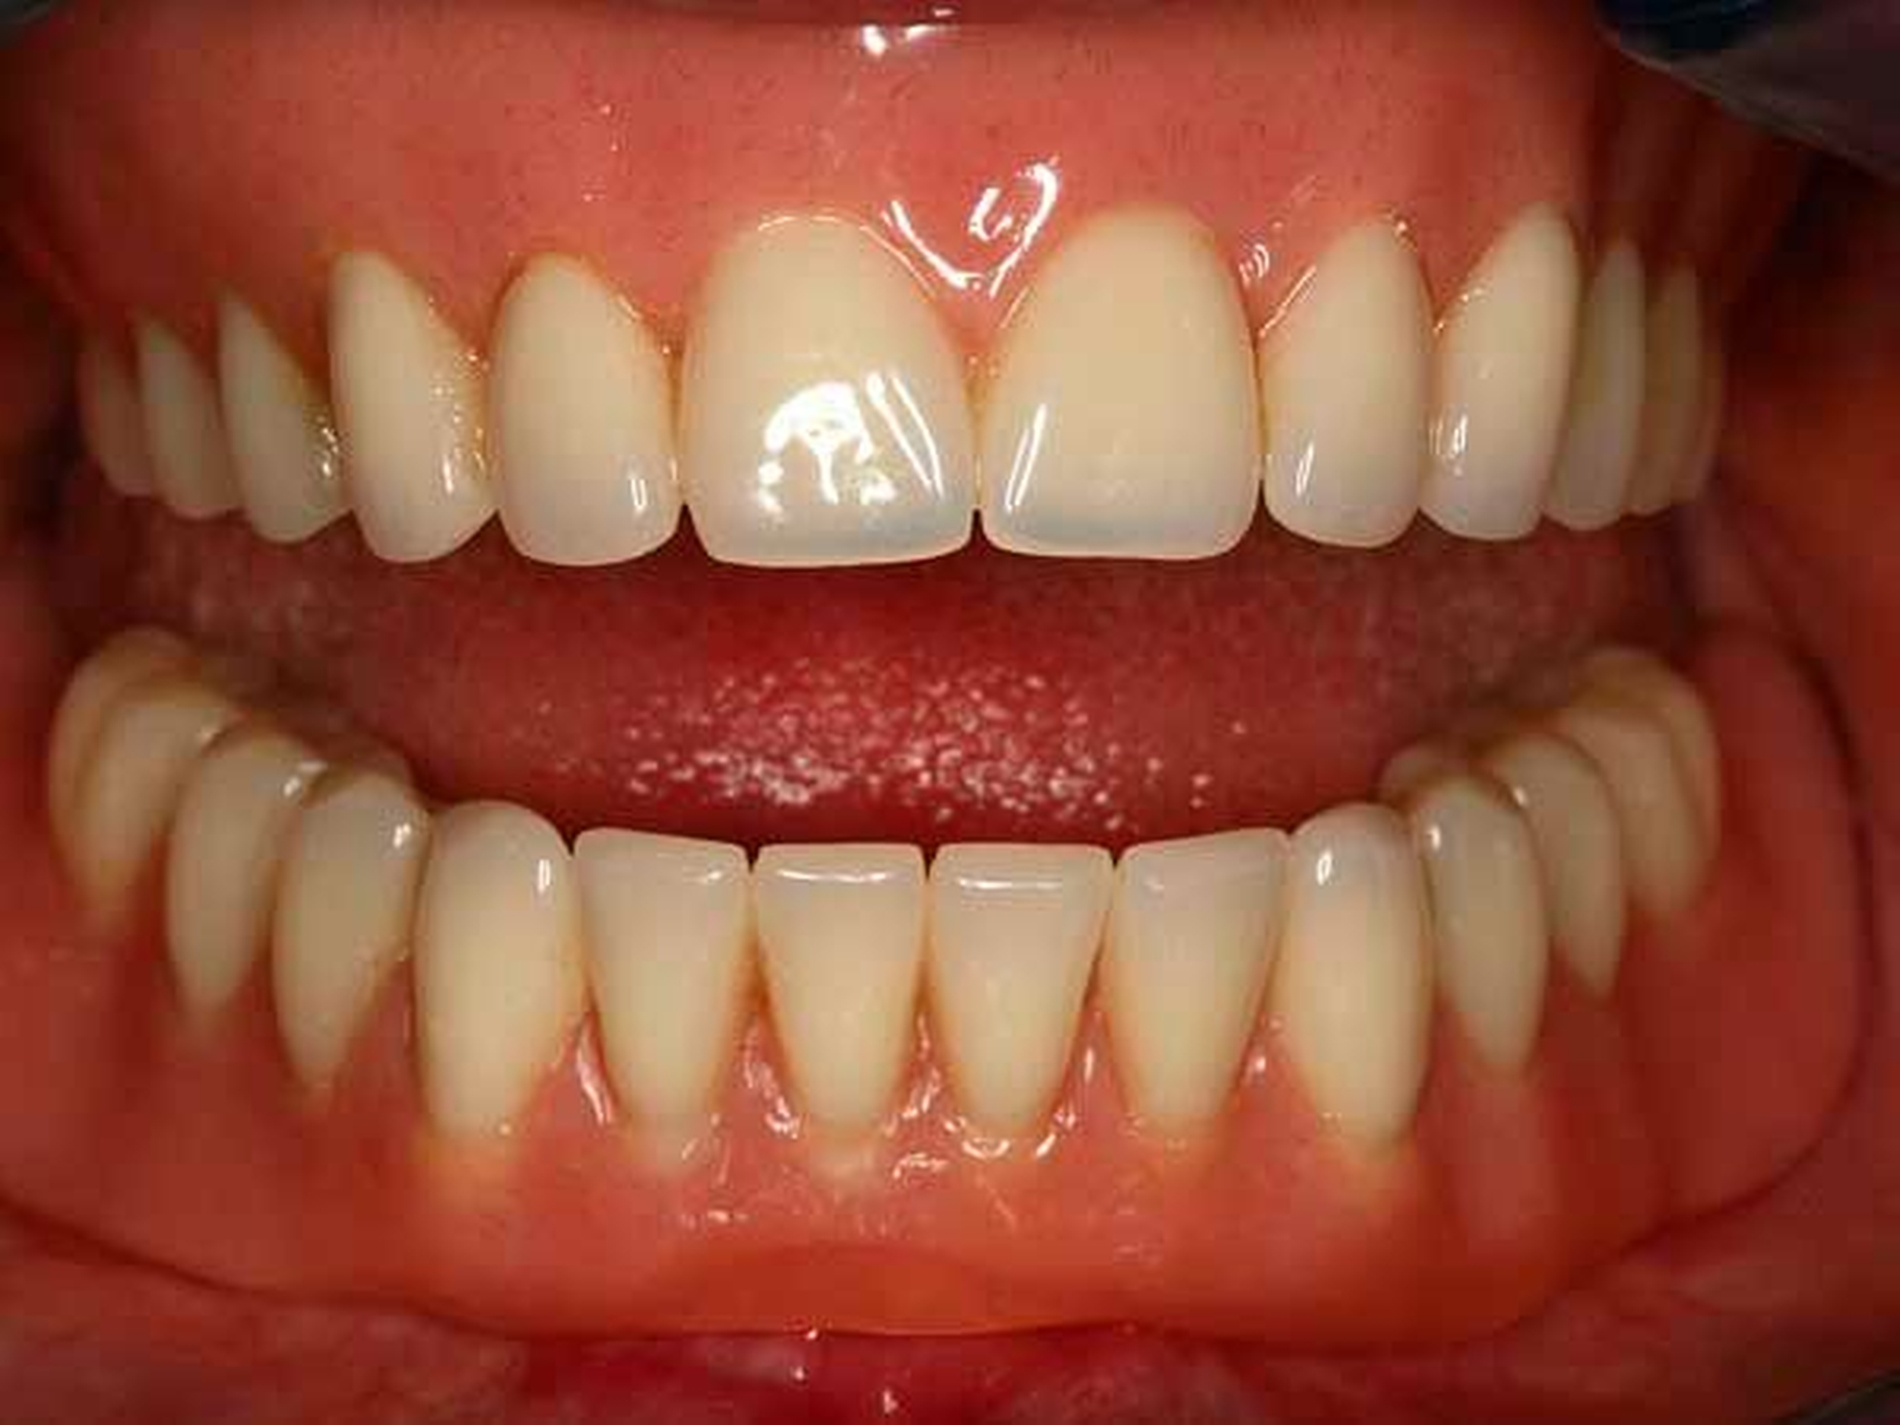

Konzept Einzelzahnimplantat: Das Konzept des mittigen Einzelimplantats im zahnlosen Unterkiefer wurde erstmals in den 1990er-Jahren von Cordioli et al. beschrieben [Cordioli G et al., 1997] (Abbildungen 1 bis 6).

Seit dieser Zeit sind zu diesem Versorgungskonzept verschiedene Untersuchungen mit heterogenen Studiendesigns durchgeführt worden, überwiegend mit einer kleinen Probandenanzahl über einen kurzen bis mittelfristigen Nachuntersuchungszeitraum von maximal fünf Jahren [Passia N, Kern M, 2014]. Diese Studien zeigten, dass das Konzept des mittigen Einzelimplantats sehr gut funktionierte, wenn die Implantate eine gestrahlte und geätzte Oberfläche aufwiesen, konventionell einheilten und das Retentionselement intraoral einpolymerisiert wurde.

Studiendesign: Hierzu wurden an neun Universitätszahnkliniken in Deutschland 158 zahnlose Patienten mit einem Implantat im Unterkiefer versorgt und entweder in die Sofortbelastungsgruppe (n = 81) oder in die Spätbelastungsgruppe (n = 77) randomisiert. In der Sofortbelastungsgruppe wurden die Implantate unmittelbar nach der Implantation mit einem Kugelkopfattachment versorgt. Die Implantate der Spätbelastungsgruppe heilten für drei Monate geschlossen ein und wurden am Tag der Freilegung ebenfalls mit einem Kugelkopfattachment versorgt (Abbildung 1).